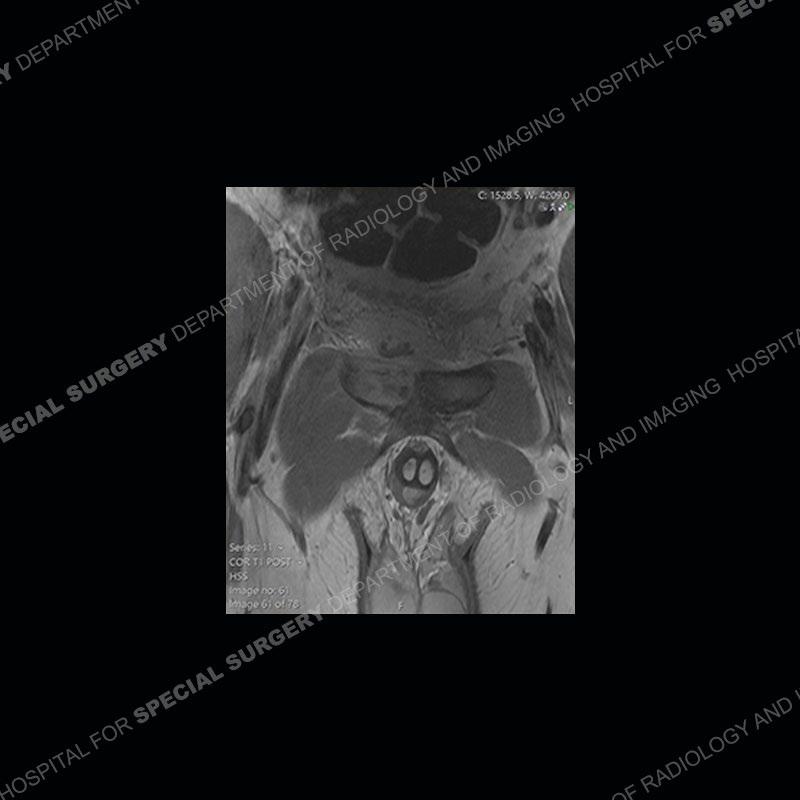

Subsequent MRI in a very short time interval shows markedly increased abnormality of the ramus and increased edema and “mass” of the soft tissue. Post contrast imaging shows multiple, rim enhancing collections of the soft tissue and similar albeit less conspicuous enhancing collection of the ramus.

Diagnosis: Osteomyelitis and Soft Tissue Abscess

The repeat MRI, with the marked degree of increased abnormality of the bone and soft tissue shifted the diagnosis to a high degree towards infection. Even the most aggressive of neoplasms would not have that the degree of change in a 3-day time span. The CT study was shown before the repeat MRI but actually occurred just after the repeat MRI. It helped confirm the destructive process of the ramus and particularly the abnormal architecture along the inferior margin. The patient went on to have a CT guided aspiration of one of the soft tissue collections with 4cc of purulent fluid obtained. A surgical irrigation and debridement of the bone and soft tissue was performed. A PICC line was placed and the patient is currently undergoing IV antibiotic treatment with a possible repeat irrigation and debridement.